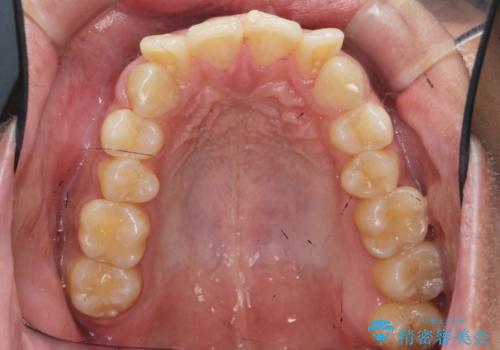

- 「前歯の見た目を改善したい。」と矯正治療を希望され来院されました。

前歯のガタつきに加え、上顎が前にある咬合関係(上顎前突)を改善すべく、マイクロインプラントを用いた上顎奥歯の後方移動、拡大、ディスキングを用いたマウスピース矯正治療を計画します。